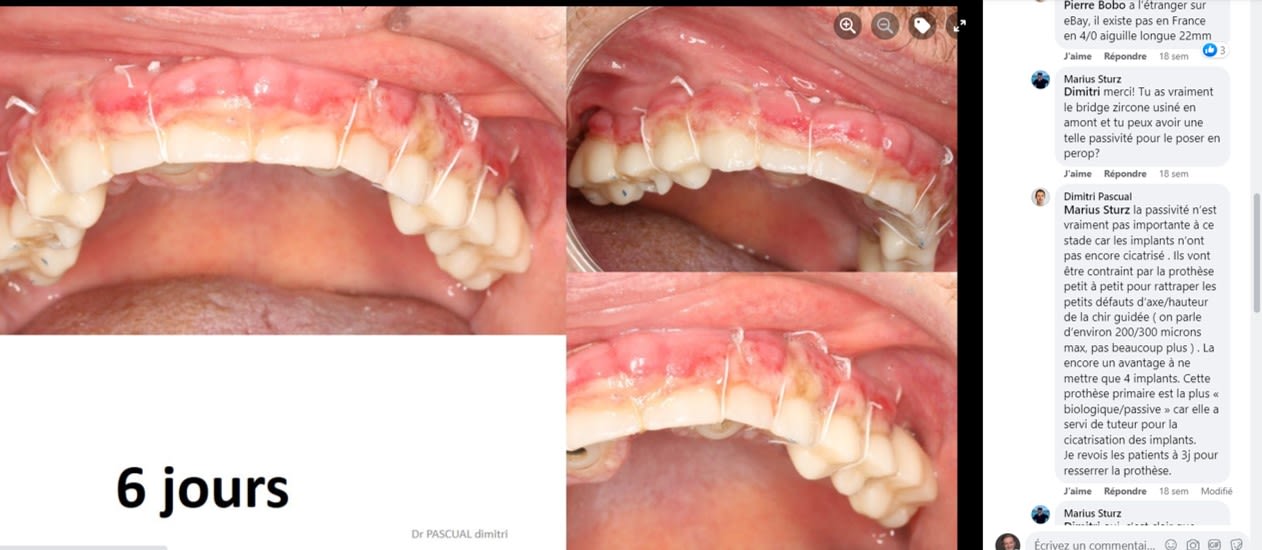

Voici ce que répond Dimitri lorsqu'on lui pose la question de la passivité:

« Marius Sturz

Dimitri merci! Tu as vraiment le bridge zircone usiné en amont et tu peux avoir une telle passivité pour le poser en perop?

Dimitri Pascual

Marius Sturz la passivité n’est vraiment pas importante à ce stade car les implants n’ont pas encore cicatrisé . Ils vont être contraint par la prothèse petit à petit pour rattraper les petits défauts d’axe/hauteur de la chir guidée ( on parle d’environ 200/300 microns max, pas beaucoup plus ) . La encore un avantage à ne mettre que 4 implants. Cette prothèse primaire est la plus « biologique/passive » car elle a servi de tuteur pour la cicatrisation des implants.

Je revois les patients à 3j pour resserrer la prothèse. »

Le principal argument de la mise en en charge immédiate est de pouvoir proposer au patient un temps réduit au maximum pour avoir une prothèse esthétique et fonctionnelle. Les patients qui réunissent le besoin et les moyens sont peu nombreux. Souvent actif, ils veulent pouvoir retrouver une présentation correcte pour reprendre leur travail sans perte de temps. A 6 jours post opératoire comment tu trouves l'aspect esthétique du cas de Dimitri PASCUAL? jeff

.

Tu peux profiter de cette photo pour lire que le bridge n'est pas passif.